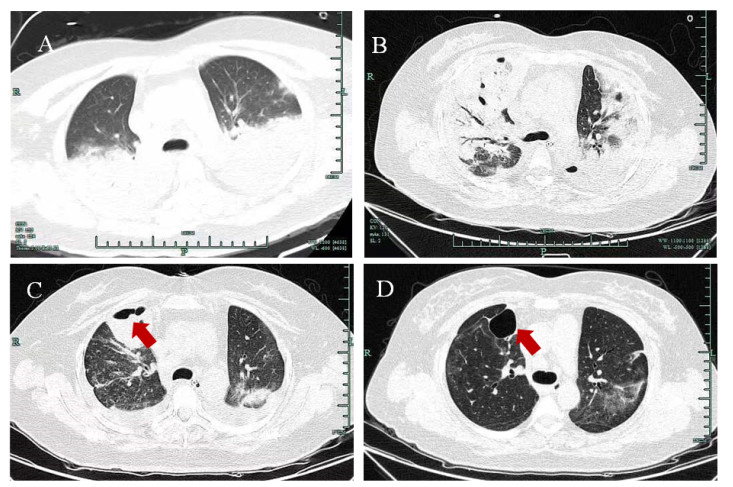

病例2为女性,55岁,因“咳嗽咳痰1月余,胸闷气急2 d”于2023-02-13入院。患者1月余前(具体日期不详)在家中无明显诱因出现咳嗽咳痰,不剧,稍感乏力,无畏寒发热,无胸闷气闭,无恶心呕吐。2023-01-08至2023-02-06曾在本院住院治疗,并诊断⑴肺部感染;⑵新型冠状病毒感染中型;⑶肺部阴影;⑷非霍奇金淋巴瘤(弥漫大B细胞淋巴瘤(GCB型)IIA期);⑸自体造血干细胞移植状态,入院后予奈玛特韦/利托那韦片抗病毒治疗及对症支持治疗、维持内环境稳定后好转出院。3 d前患者走路后出现胸闷气急,休息可缓解,为求治疗来本院就诊,复查胸部CT提示两肺多发感染,双侧胸膜肥厚,对比2023-02-02两肺感染灶增多(图 2A),门诊拟“肺部重症感染”收住呼吸内科。既往确诊非霍奇金淋巴瘤[弥漫大B细胞淋巴瘤(GCB型)ⅡA期]9月余,曾感染新型冠状病毒,有新冠疫苗接种史。患者于2023-02-19因血氧饱和度下降,予气管插管后转入重症医学科进一步监护治疗。入科查体:体温37.5℃,呼吸22次/min,心率122次/min,血压153/126 mmHg。意识药物镇静,气管插管接呼吸机辅助通气(AC+PC模式,FiO2:45%,PEEP:12 cmH2O),全身皮肤、巩膜无黄染,锁骨上下淋巴结未触及肿大,双肺可闻及少许湿啰音,心腹查体无特殊。入院实验室检查:动脉血气分析(呼吸机纯氧支持)pH 7.502,氧分压100 mmHg,二氧化碳分压27.9 mmHg,碳酸氢根21.7 mmol/L,剩余碱-0.5 mmol/L,乳酸2.8 mmol/L。血常规:WBC 2.8×109/L,NEU% 73.6%;CRP 60.73 mg/L;肝功能:ALT 55 U/L,AST 39 U/L,ALB 31.5 g/L;CK 20 U/L,LDH 341 U/L;肾功能、凝血功能大致正常;肺炎衣原体抗体IgM 0.03 COI,IgG 26.40 AU/mL,呼吸道抗体均为阴性,新型冠状病毒核酸检测阳性。辅助检查:2023-02-19胸部CT提示两肺多发感染(部分肺组织实变),双侧胸腔少量积液,对比2023-02-10两肺病变及胸腔积液增多(图 2B)。入科诊断:⑴重症肺炎;⑵基础疾病危重型合并新型冠状病毒感染;⑶急性呼吸衰竭;⑷非霍奇金淋巴瘤[弥漫大B细胞淋巴瘤(GCB型)IIA期];⑸自体造血干细胞移植状态;⑹继发性血小板减少;⑺白细胞减少;⑻胸腔积液。治疗上予亚胺培南西司他丁钠(1.0g ivgtt q8h)联合莫西沙星(0.4g ivgtt qd)、复方甲恶唑片(0.96 g营养管滴入q12h)抗感染,同时予呼吸机支持、镇痛镇静、俯卧位通气、抗病毒、激素抗炎、低分子肝素抗凝、化痰解痉、保肝护胃、维持内环境稳定及对症支持治疗。2023-02-20行气管镜检查并留取BALF送检mNGS。2023-02-22 mNGS结果提示找到白色念珠菌、鹦鹉热衣原体、新型冠状病毒(2019-nCoV),序列数分别2 127、9、24 755条,追问病史,患者为农民,常年住在乡下,家中饲养家禽,否认饲养鹦鹉、鸽子等鸟类。据此,考虑患者为新型冠状病毒合并鹦鹉热衣原体感染所致重症肺炎,同时有白色念珠菌感染,予停用美罗培南、复方磺胺甲恶唑片,改为阿奇霉素(0.5 g ivgtt qd)联合莫西沙星(0.4g ivgtt qd)抗感染,卡泊芬净(50 mg ivgtt qd)(首剂70 mg)抗真菌治疗。2023-02-23复查胸部CT提示两肺多发感染,双侧胸膜增厚,对比2023-02-19两肺病变及胸腔积液部分吸收(图 2C)。患者经对症支持治疗后呼吸氧合改善,于2023-03-06顺利拔除气管插管。2023-03-09复查胸部CT提示两肺多发感染,部分实变,双侧胸膜增厚,对比2023-03-03两肺感染局部稍吸收(图 2D)。2023-03-10转呼吸内科普通病房进一步抗感染治疗。因患者既往有血液系统疾病,长期处于免疫功能低下状态,且合并新型冠状病毒、鹦鹉热衣原体及白色念珠菌感染,住院期间反复出现发热,三系进行性下降,2023-03-15再次出现病情恶化,经加强抗感染及对症支持治疗后效果不佳,最终于2023-03-19死亡。

| A:双肺多发感染;B:双肺感染较前增加;C:肺部感染较前吸收;D:肺部感染较前吸收 图 2 病例2胸部CT检查结果 |